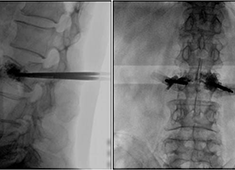

C臂机在打骨水泥时是怎么使用的(PKP手术记录)

在打骨水泥时通常要借助C臂机来进行,具体是如何使用的呢?下面通过南京医科大学第二附属医院的一则手术案例来深入学习。首先将患者处于俯卧位,然后利用普爱大平板C臂机摆位灵活的特点,快速定位椎弓根位置...